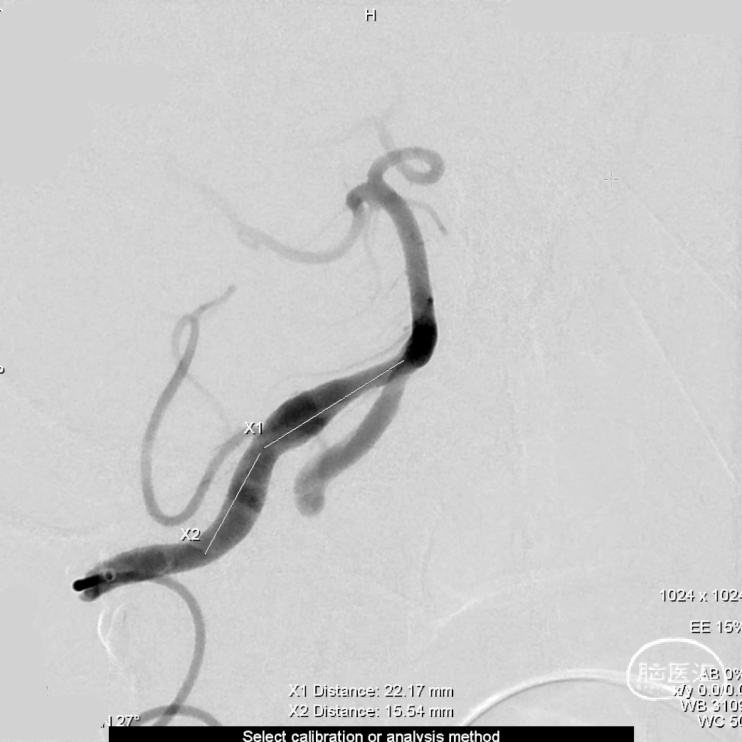

术前测量:

覆盖长度:37mm

动脉瘤内有血栓,部分不显影。

直径:

瘤颈远端:3.83mm

瘤颈近端:4.71mm

近端锚定点:3.73mm

选择Lattice血流导向密网支架

5.3mm*37mm,8个球囊